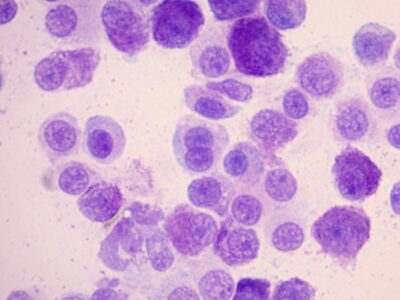

anaplasma inclusions

anaplasma inclusions -

anaplasma inclusions

anaplasma inclusions -